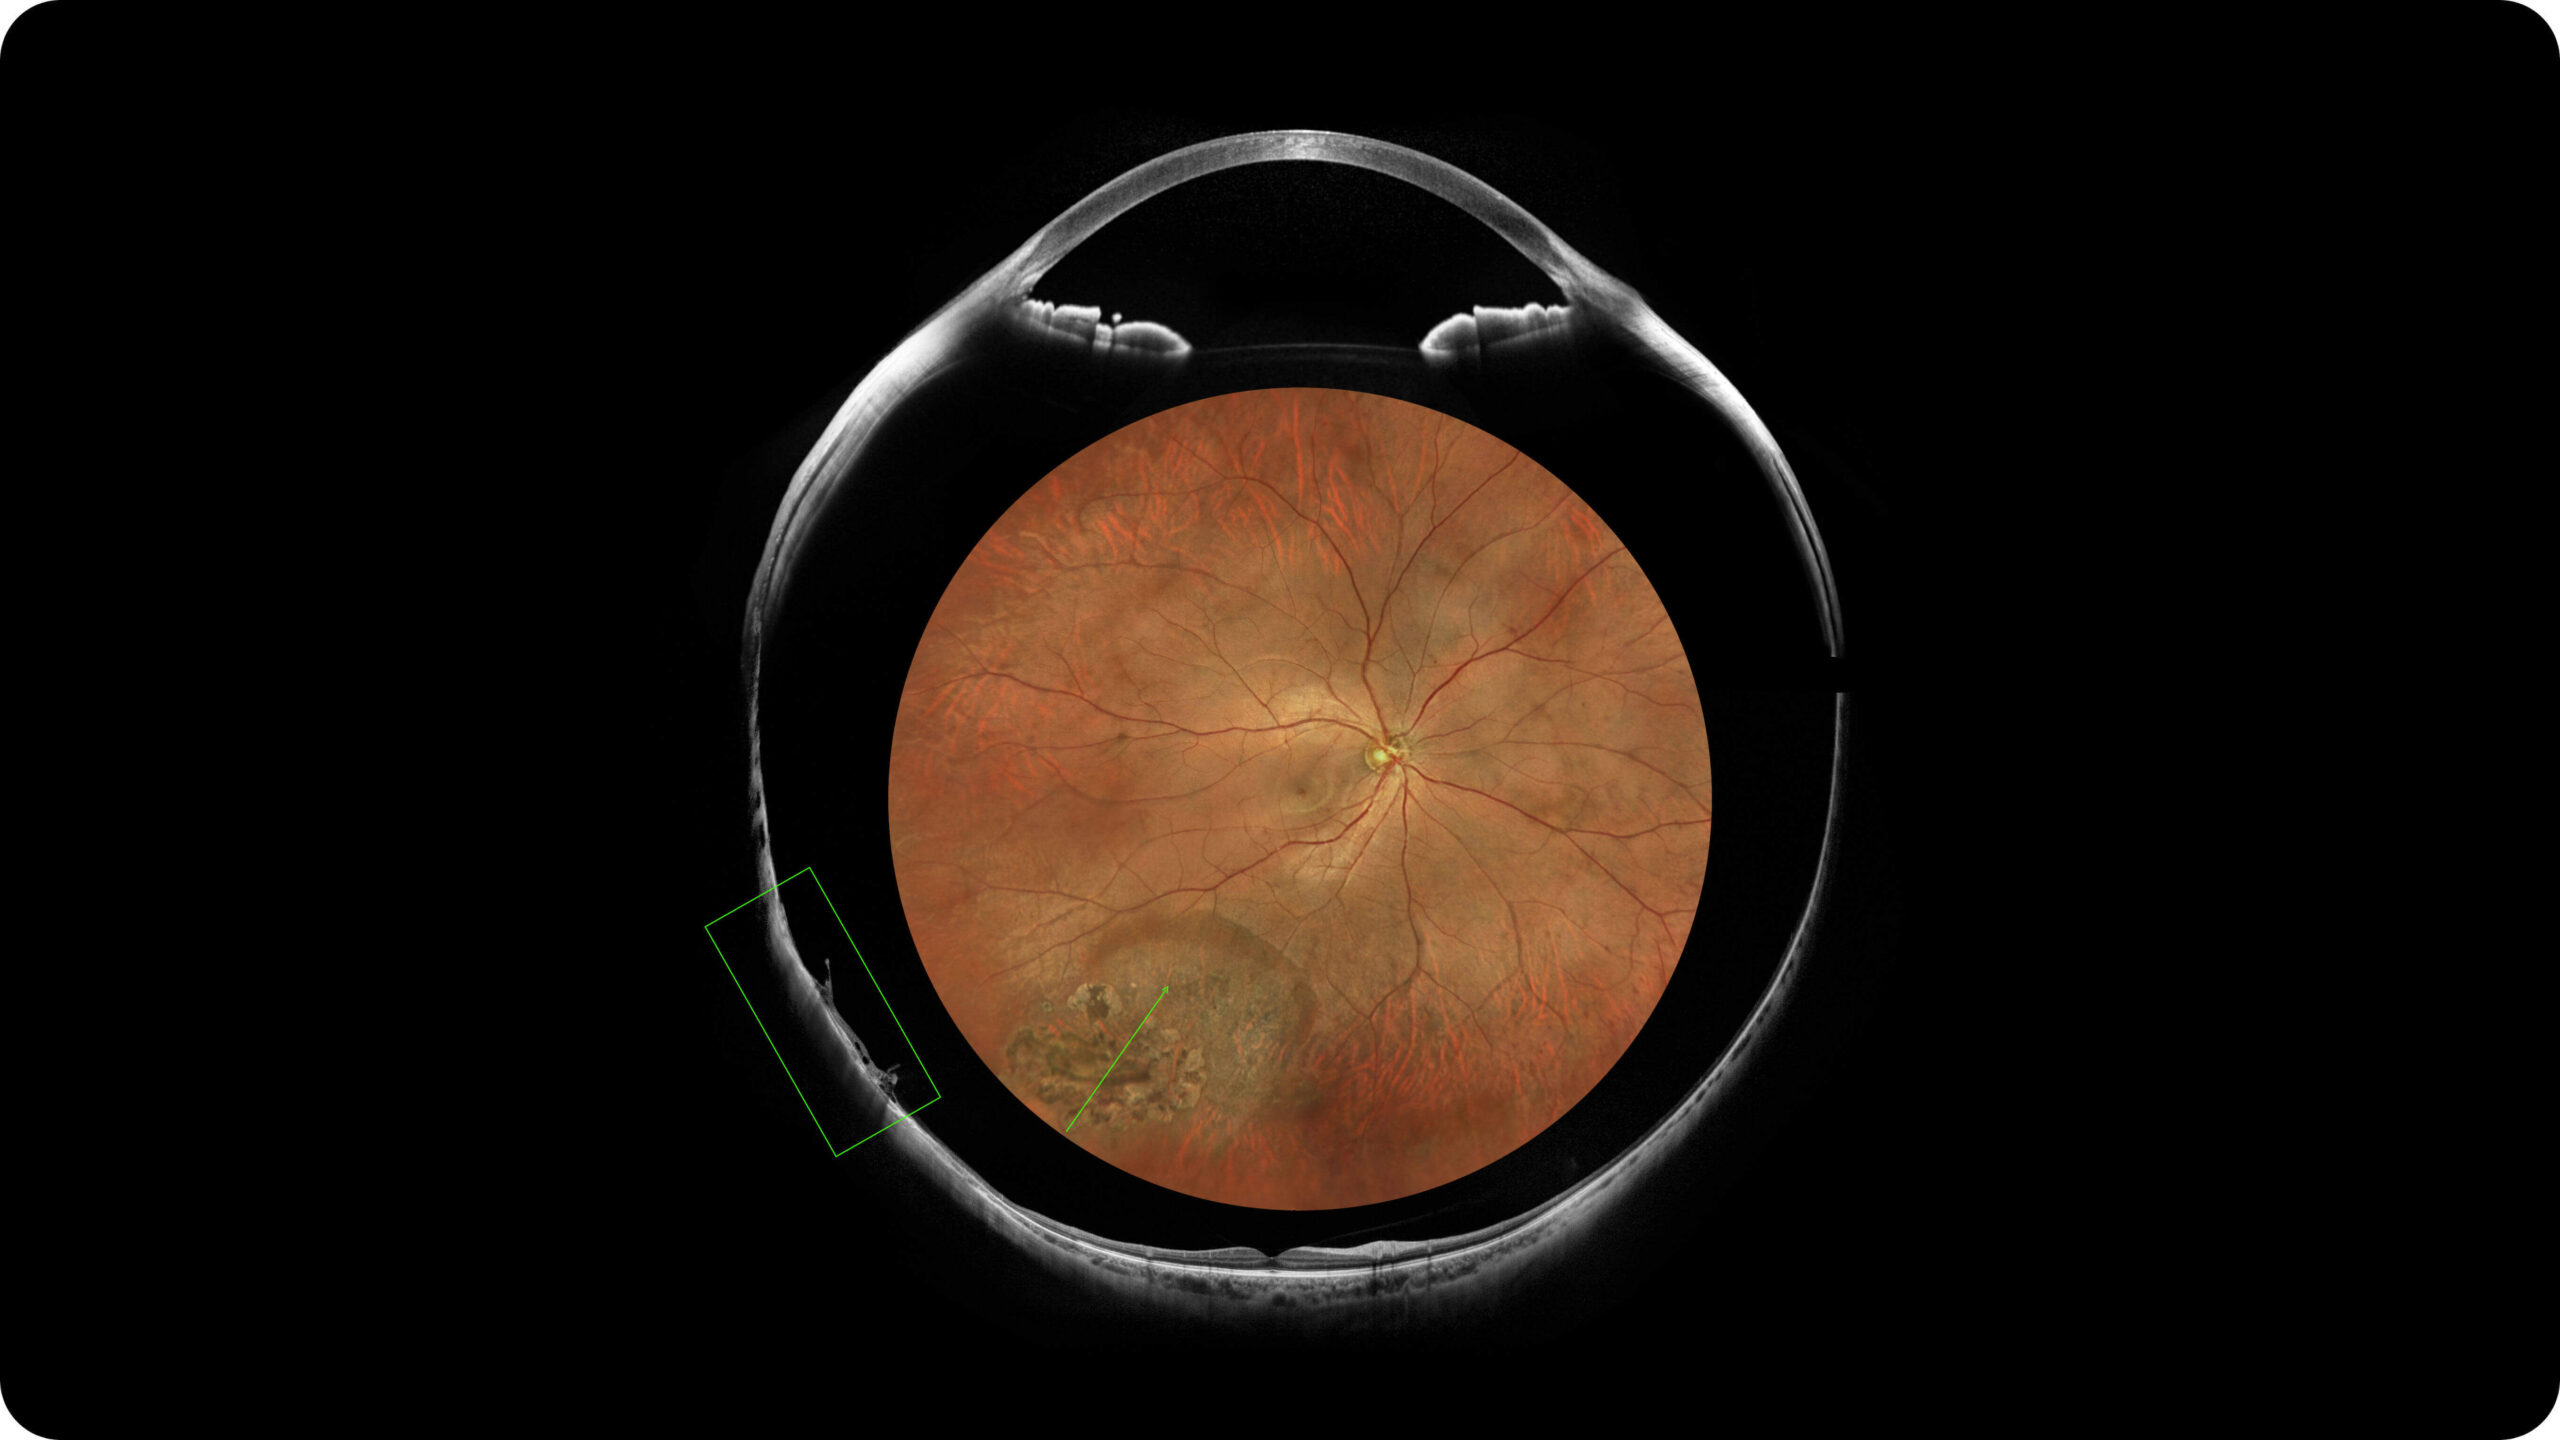

Olho Inteiro

Uma única varredura pode obter rapidamente imagens sincronizadas de imagens coloridas de campo ultralargo/FAF/FFA/ICGA e SS-OCT, alcançando sincronização em tempo real e alinhamento preciso de imagens planas e estruturais da retina, melhorando significativamente a eficiência da inspeção e otimizando o processo de diagnóstico e tratamento.” Uma única varredura pode obter rapidamente imagens sincronizadas de imagens coloridas de campo ultralargo/FAF/FFA/ICGA e SS-OCT, alcançando sincronização em tempo real e alinhamento preciso de imagens planas e estruturais da retina, melhorando significativamente a eficiência da inspeção e otimizando o processo de diagnóstico e tratamento.

Multi-Modalidade

Altamente integrado com tecnologias como SLO confocal e SS-OCT, ele combina imagens coloridas SLO de campo ultralargo, angiografia confocal a laser, autofluorescência e imagens tomográficas de segmento anterior e posterior ultraamplas e profundas em um único sistema.